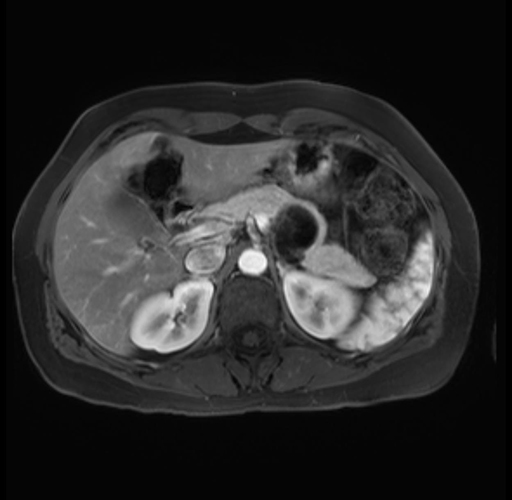

Imaging Analysis

Look through the patient's CT scan to identify any areas of concern for the necessary procedure.

Based on your CT findings, which issue(s) are present and would give reason for "planned slowing down moment(s)" in this case?